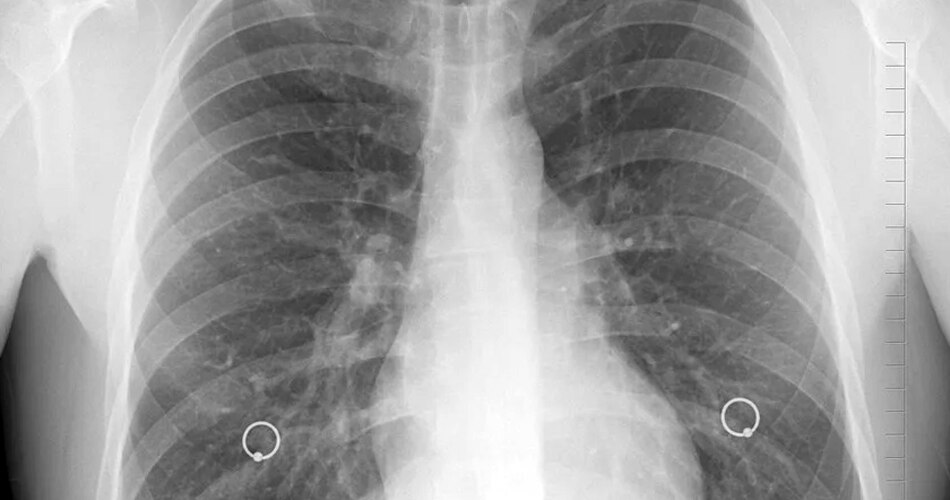

लंग कैंसर

सभी तरह के कैंसर में लंग यानी फेफड़ों का कैंसर सबसे आम है. इसकी एक खास वजह स्मोकिंग मानी जाती है. इसलिए फेफड़ों को बचाने के लिए सिगरेट ना पीने की सलाह दी जाती है. हालांकि, ये धारणा पूरी तरह गलत है कि स्मोक ना करने से आपको फेफड़ों का कैंसर नहीं होगा.

लंग कैंसर1